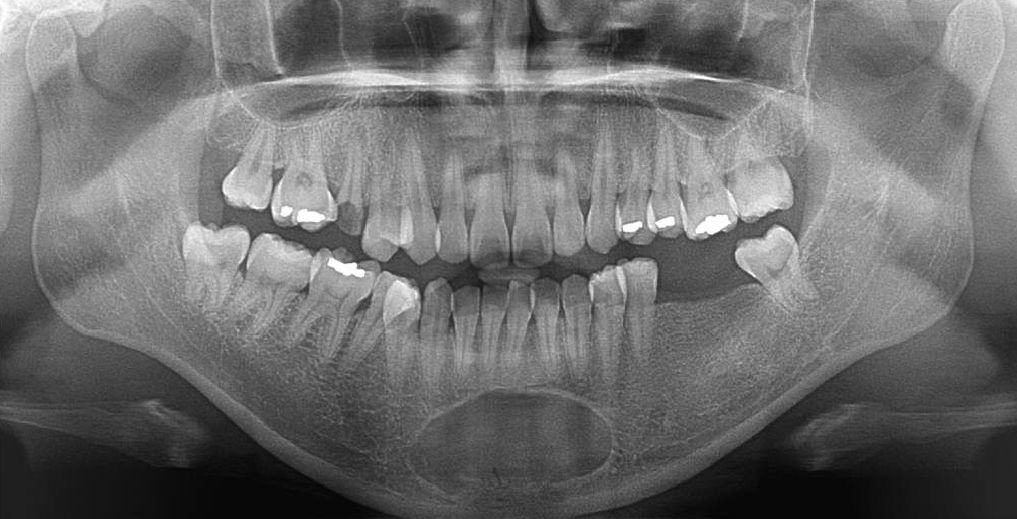

치근단병소로 오인된 하악치아의 백악질골형성이상 ; 콘빔CT 기반 증례보고

한원정

J Korean Dent Assoc.

2024;62(7):432-438. Published online July 30, 2024

DOI:

https://doi.org/10.22974/jkda.2024.62.7.002